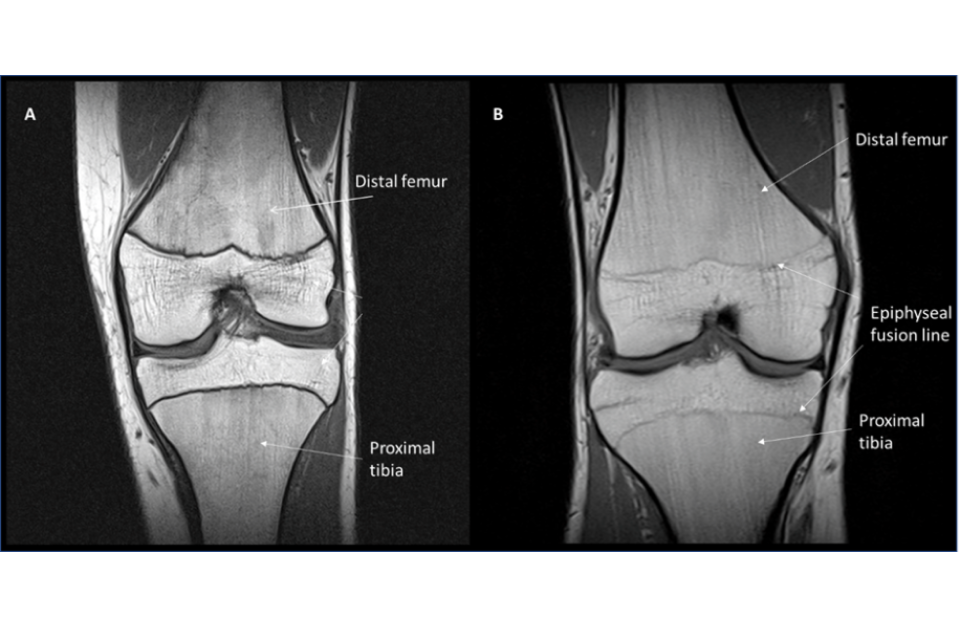

4.48. Assessment of age using MR imaging of the knee has a more recent supporting bibliography than the use of radiography of the hand/wrist, and there is a growing body of international research to support its use. The assessment of age using the knee relies on changes to the appearance of the bones – changes to shape and fusion between the epiphysis and the diaphysis at both the distal end of the femur and the proximal end of the tibia. When this fusion starts to occur, an epiphyseal fusion line is visible by MRI (see Figure 6) and can persist for some time after fusion is complete.

Figure 6: Magnetic Resonance images of the knee of a male aged 15 years (A) and a male aged 17 -years (B)

MRI described above